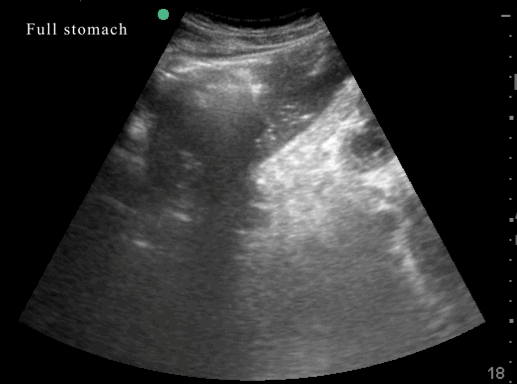

- Is the stomach empty or full ?

- Does the content in the stomach represent a risk for the patient ?